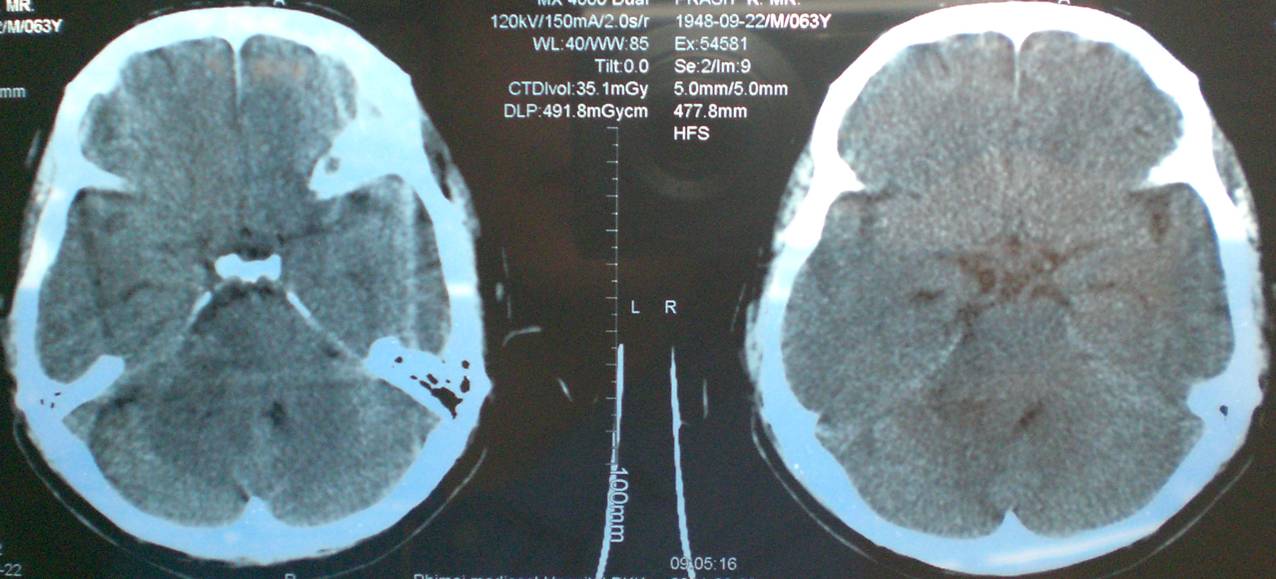

Cavernous Angioma Of The Cerebellopontine Angle

Cerebellopontine Angle Charles A. Cotton, MD,a Douglas P. Beall, MD,a Bart J. Winter, BS,b sent the tumor to surgical pathology after it was resected and the histopathological evaluation was consistent with a cavernous angioma. Immediately ... Read More